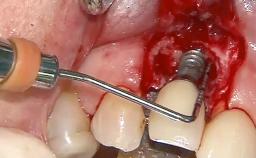

Treatment of Peri-Implantitis at a Zirconia Implant

Frank Schwarz, Ausra Ramanauskaite

Due to their promising clinical performance, zirconia implants have recently become popular alternatives to titanium implants, particularly for areas with high esthetic demands (Holländer and coworkers 2016; Roehling and coworkers 2016; Lorenz and coworkers 2019). However, regardless of the reported high survival and success rates, zirconia implants were affected by peri-implant diseases over the short observation period, suggesting the importance of treating peri-implant diseases at zirconia implants (Becker and coworkers 2017). In their case, Frank Schwarz and Ausra Ramanauskaite present 3-year results following mechanical debridement alongside Er:YAG laser monotherapy.